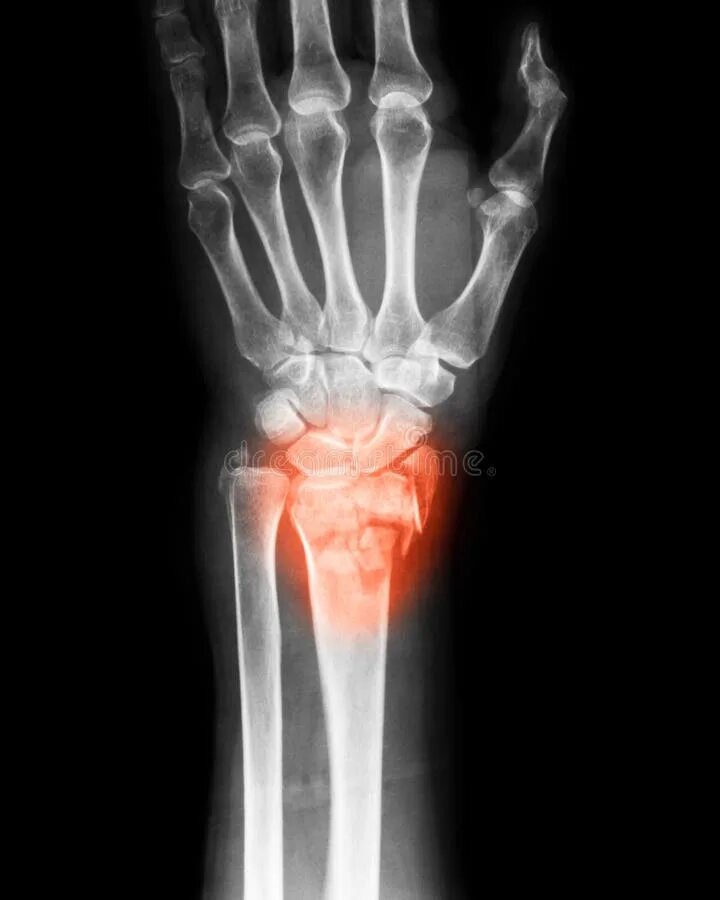

Перелом лучезапястного сустава лечение